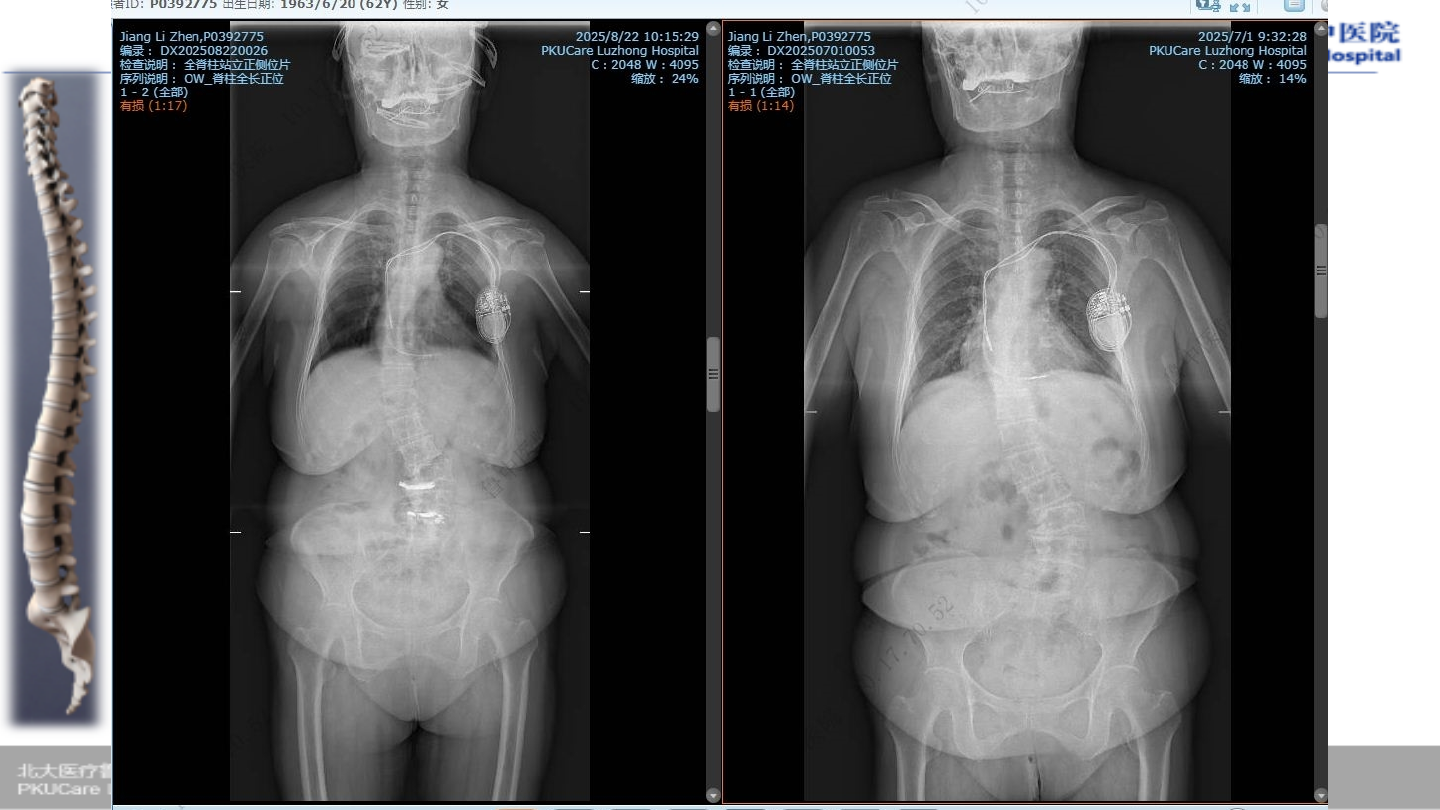

术前腰椎

X-ray

术前